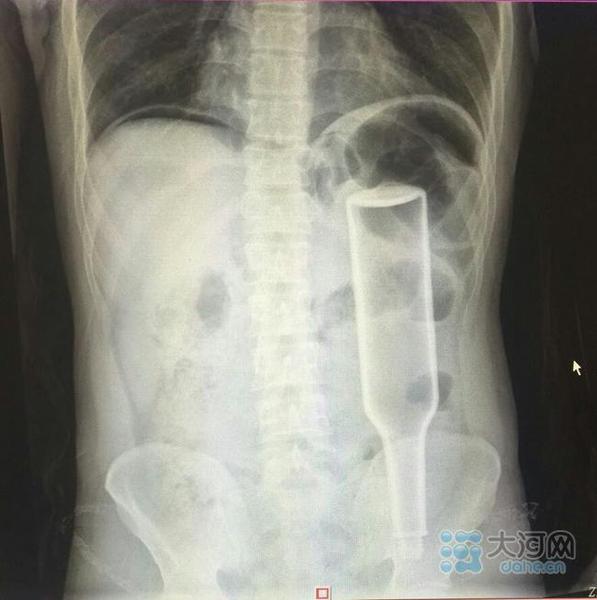

看这片子,花露水瓶子已经很“深入”了。

在郑州务工的外地男子王某,下班到家后闲着没事儿干,于是将一个长18厘米的花露水瓶子塞进了自己的肛门,不过因为用力过猛,快感没来,瓶子却把直肠给戳破了,疼得受不了了,王某羞答答地来到郑州人民医院就诊,医生给他做了手术,现在已经出院。

“医生,我肚子很痛,快帮我看看。”两周前,30多岁的王某捂着肚子来到郑州人民医院求助。对于病情,王某一开始并没有告诉医生,只是说自己肚子疼得受不了。随后在检查中,该院普外一病区张春礼大夫发现,王某的下腹部内显示有一个完整玻璃瓶的模样。

在医生的详细询问下,王某才不好意思地道出隐情。他说自己在家试着把花露水瓶塞到肛门中,没想到用力过猛,瓶子完全塞进腹腔,肚子越来疼痛难忍,没办法,他才到医院找医生。